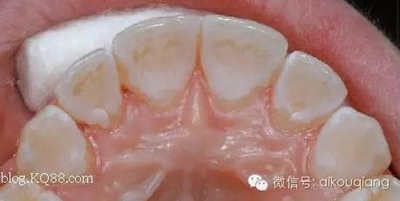

發(fā)幾張漂亮有個性的哈氏活動保持器: